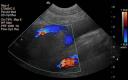

In the acute phase, thrombi in the arterial or venous systems are typically anechoic. These can be caused by migration of a fragment of thrombus from the left atrium to the terminal aorta (such as cats with cardiomyopathy), or a portal vein thrombus that causes portal hypertension and ascites. Acutely formed thrombi are anechoic. You may see some faint echogenicity within the vessel, but these are usually diagnosed using Doppler ultrasound. The color flows around the filling defect in the vessel.

The location of the thrombus determines whether it causes clinical signs. Arterial thrombi, such as in the aorta, can occlude blood flow to distal structures. Ischemia of the hind limbs is a common complication of aortic thrombosis as the thrombus can occlude or extend down the iliac arteries. An aortic thrombus can also occlude the renal arteries causing renal ischemia. The thrombus in image 1 (*) is very close to the renal artery (R) but not occluding it. Portal vein thrombosis is also usually clinical because of the ascites that forms from portal hypertension. Thrombi in the splenic veins are very common, and don’t usually cause any symptoms. These can be an incidental finding (Image 2 and 3), such as in this dog with lymphoma who had been treated with prednisone.